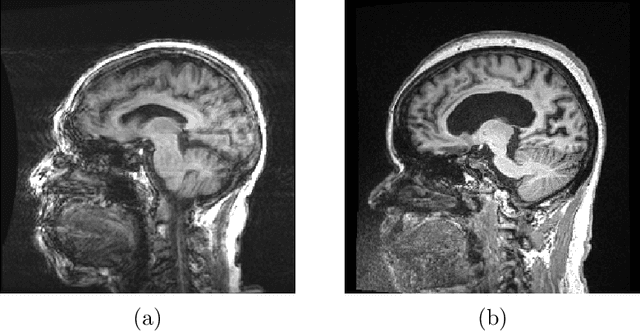

Abstract:Combining multi-site data can strengthen and uncover trends, but is a task that is marred by the influence of site-specific covariates that can bias the data and therefore any downstream analyses. Post-hoc multi-site correction methods exist but have strong assumptions that often do not hold in real-world scenarios. Algorithms should be designed in a way that can account for site-specific effects, such as those that arise from sequence parameter choices, and in instances where generalisation fails, should be able to identify such a failure by means of explicit uncertainty modelling. This body of work showcases such an algorithm, that can become robust to the physics of acquisition in the context of segmentation tasks, while simultaneously modelling uncertainty. We demonstrate that our method not only generalises to complete holdout datasets, preserving segmentation quality, but does so while also accounting for site-specific sequence choices, which also allows it to perform as a harmonisation tool.

Abstract:Being able to adequately process and combine data arising from different sites is crucial in neuroimaging, but is difficult, owing to site, sequence and acquisition-parameter dependent biases. It is important therefore to design algorithms that are not only robust to images of differing contrasts, but also be able to generalise well to unseen ones, with a quantifiable measure of uncertainty. In this paper we demonstrate the efficacy of a physics-informed, uncertainty-aware, segmentation network that employs augmentation-time MR simulations and homogeneous batch feature stratification to achieve acquisition invariance. We show that the proposed approach also accurately extrapolates to out-of-distribution sequence samples, providing well calibrated volumetric bounds on these. We demonstrate a significant improvement in terms of coefficients of variation, backed by uncertainty based volumetric validation.